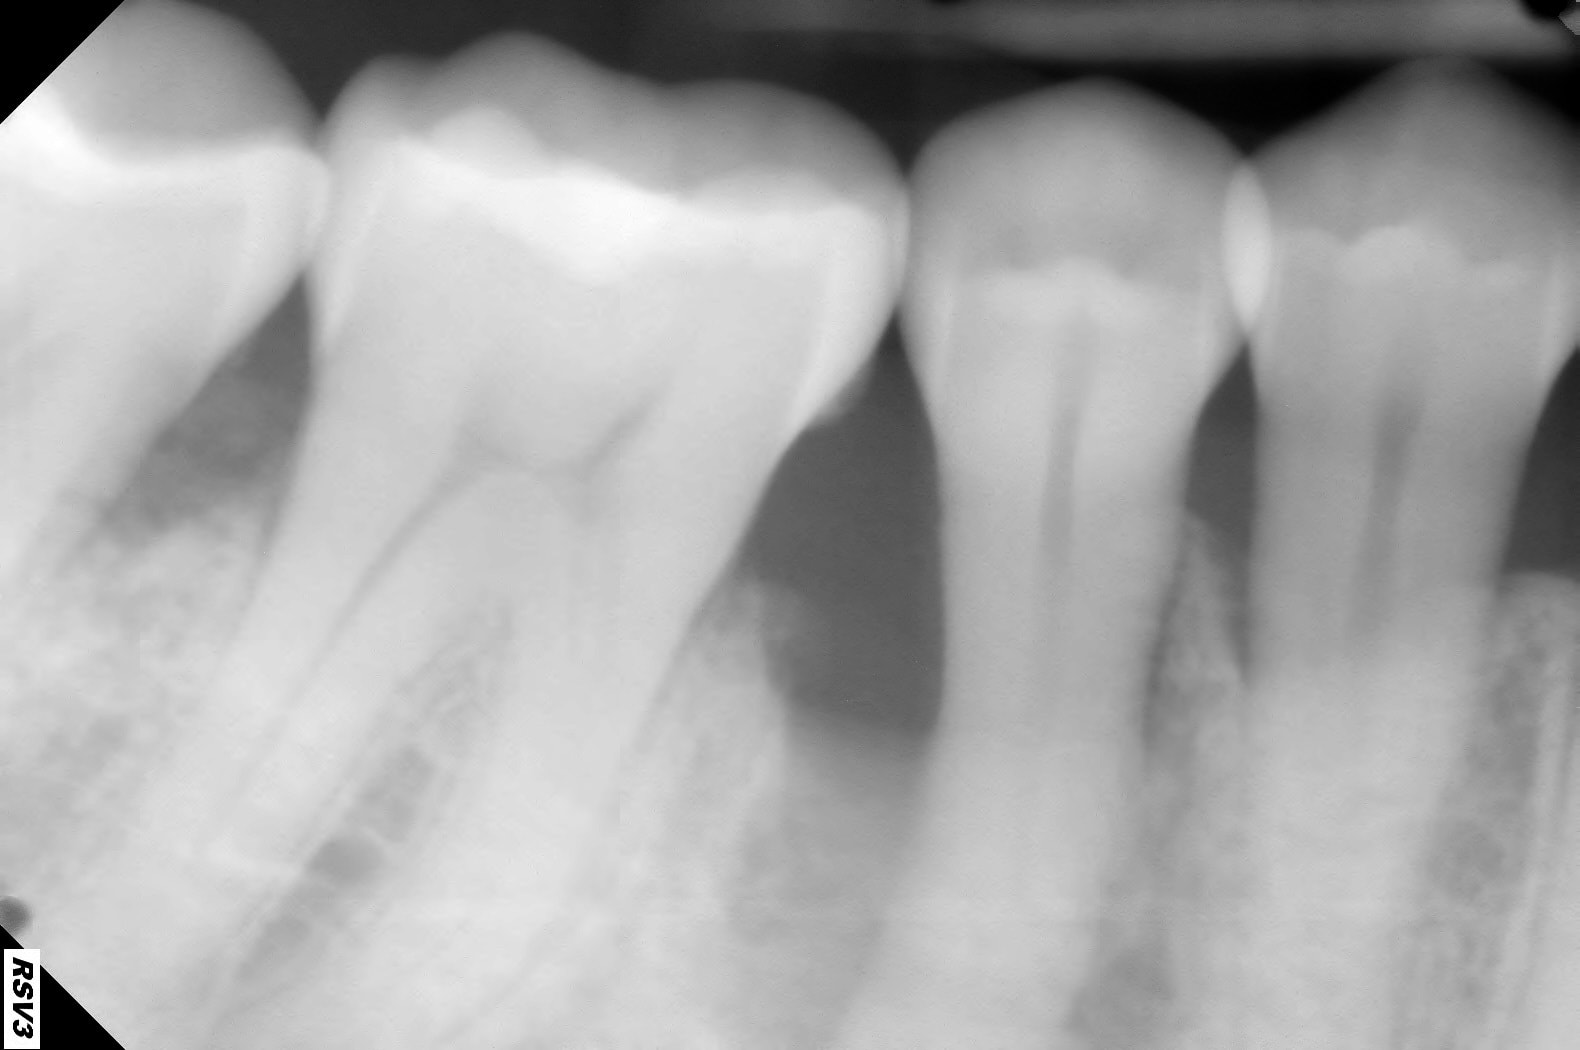

Voici la rétro de la 45 mais je n'ai pas celle de la 12.

Je pense que l'image au dessus de 12 sur l'opt est un artéfact.

... c est mal barré quand meme.

pourquoi pas, c est pas totalement perdu.

Avec l’apex, histoire de pouvoir coter…

Je mettrais un billet qu’elle est bien vivante et qu’il n’y a aucune douleur 🧐